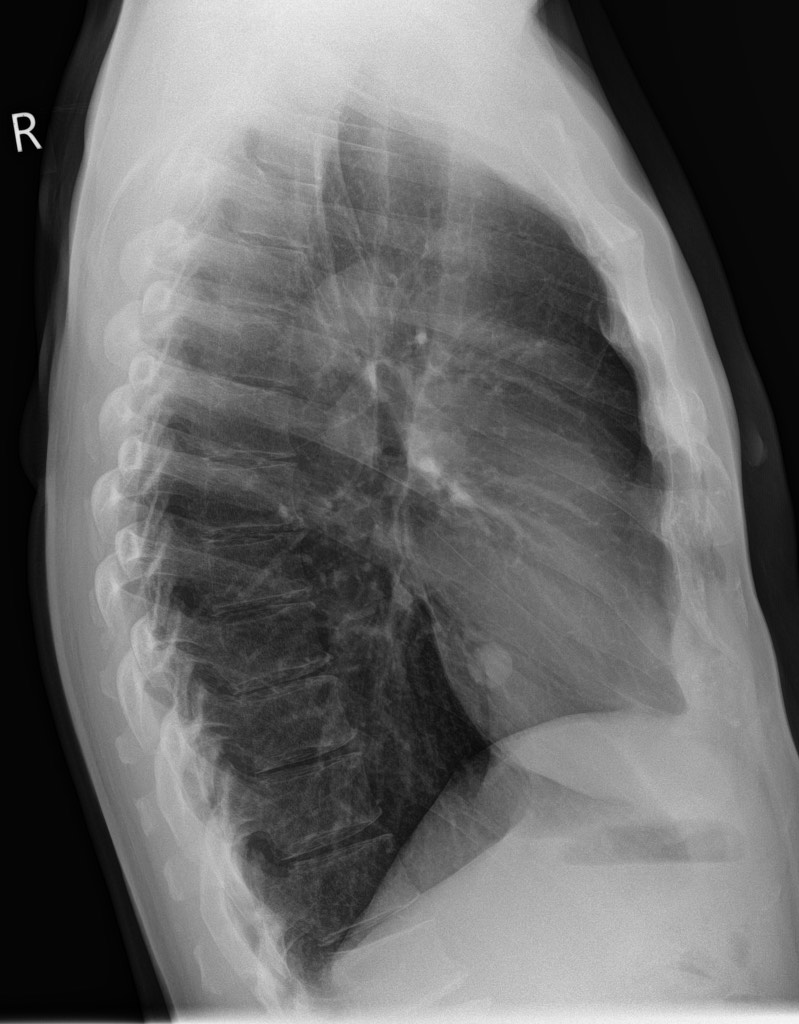

2986. Учитывая представленные на рентгенограммах

и данные и локализацию первичного железистого рака в лёгком, целесообразно выполнение ____________________ с удалением регионарных лимфоузлов